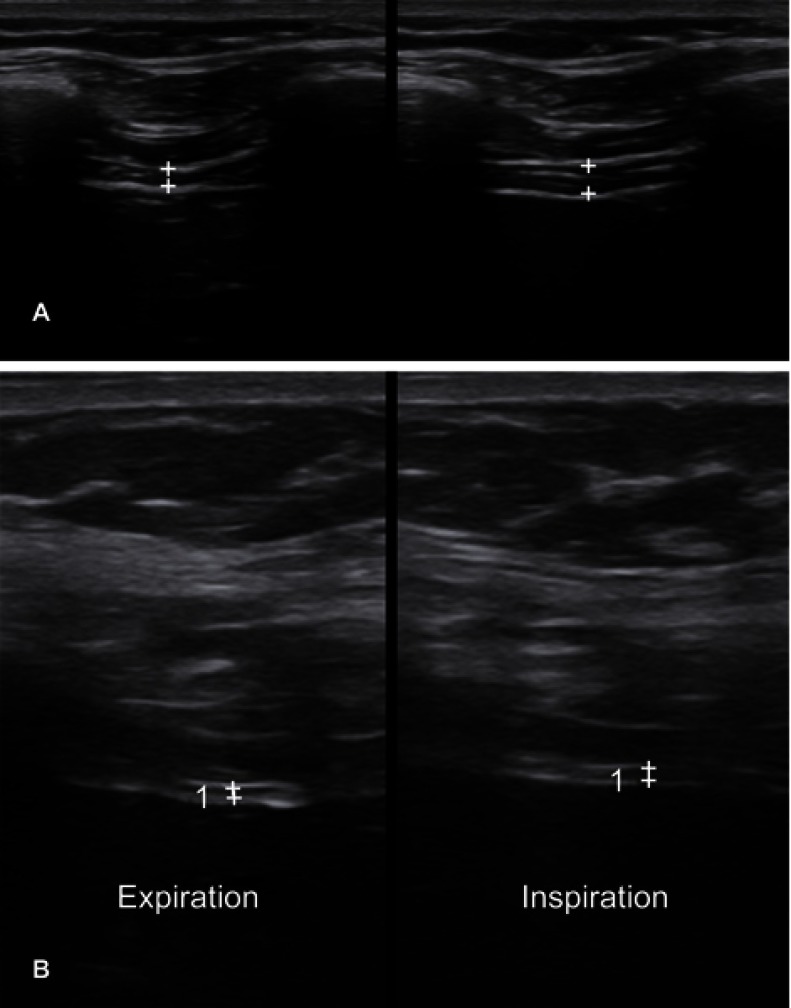

Amyotrophic lateral sclerosis (ALS) is a devastating neurodegenerative disorder characterized by dysfunction at multiple levels of the neuraxis. It remains a clinical diagnosis without a definitive diagnostic investigation. Electrodiagnostic testing provides supportive information and, along with imaging and biochemical markers, can help exclude mimicking conditions. Neuromuscular ultrasound has a valuable role in the diagnosis and monitoring of ALS and provides complementary information to clinical assessment and electrodiagnostic testing as well as insights into the underlying pathophysiology of this disease. This review highlights the evidence for ultrasound in the evaluation of bulbar, limb and respiratory musculature and peripheral nerves in ALS. Further research in this evolving area is required.